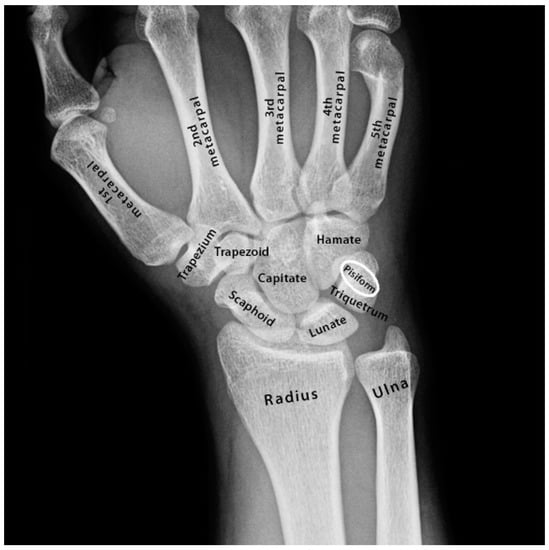

3.2. Restricted Wrist Rotation Associated with Evolutionary Retrograde Wrist Morphology

- Pisiform and its elongation (retrogression) and extension into the radio-ulnar joint that restricted wrist rotation.